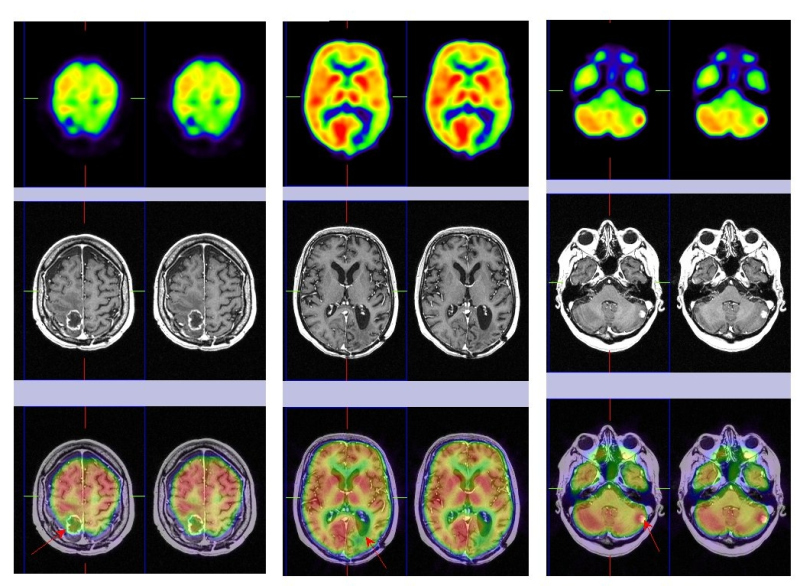

Al cabo de 5 meses la paciente refiere cefaleas y hemiparesia izquierda, realizándose una RM de urgencia que detecta un crecimiento de la lesión parietal derecha con realce periférico, captación heterogénea de contraste y edema perilesional, no mostrando cambios significativos las otras dos lesiones parieto-occipital y cerebelosa izquierdas. Se decide realizar un estudio PET-RM cerebral de control (fig. 2), donde se observa captación patológica de la 18F-FDG en la lesión aumentada de tamaño en lóbulo parietal derecho, que refleja recidiva tumoral y sin cambios en las restantes lesiones conocidas (radionecrosis).

Al cabo de 3 meses refiere de nuevo deterioro neurológico presentando cefalea, inestabilidad en la marcha y acentuación de la hemiparesia izquierda. Se le realiza una RM cerebral de urgencia que muestra una cavidad porencefálica en lóbulo parietal derecho secundaria a cirugía, persiste la radionecrosis parieto-occipital izquierda y hay un incremento del tamaño de la lesión cerebelosa izquierda que se interpreta como recidiva tumoral. Tras el hallazgo de la RM se realiza nuevo estudio PET-RM de control (fig. 3) que detecta fijación patológica de la 18F-FDG en la lesión cerebelosa izquierda indicando recidiva tumoral maligna, ausencia de captación en lóbulo parietal derecho (cambios quirúrgicos) y en región parieto-occipital izquierda (radionecrosis). Ante dicha situación, se decide la extirpación quirúrgica de la metástasis cerebelosa izquierda y en la evolución se objetiva mejoría clínica.